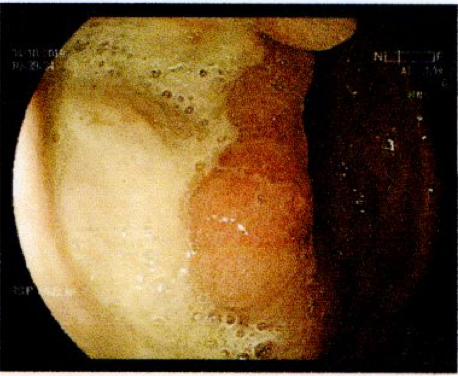

Gastric abnormalities show nonspecific gastrointestinal symptoms and similarly radiological findings. Intra and extra luminal gastric wall thickening are the most common finding in benign and malignant pathologic process. This aim of this case report was to describe several characteristics such as the location and size of the lesion, involvement of the gastric wall and surrounding structures, calcifications, and contrast enhancement pattern which can assist in radiological diagnosis. Several cases at our institution have similar gastrointestinal complaints, however, there were different lesions characteristic found in contrast enhanced abdominal CT scan. The first case 72-years-old man experienced hematemesis with radiologic finding diffuse gastric mucosal thickening as well as homogenous contrast enhancement but without calcification. The second case 37-years-old man complaint dizziness and melena with radiologic finding large tumor more than 10 cm in size, amorph calcification and heterogenous contrast enhancement. The last 60-years-old man case experienced melena and hematemesis, from abdominal CT scan showed irregular gastric mucosal thickening with heterogenous contrast enhancement and fat stranding around the lesion, without calcification. Methods used in these cases were contrast-enhanced abdominal CT scan, esophagogastroduodenoscopy (EGD), and biopsy in order to determine the diagnosis. Contrast-enhanced abdominal CT scan plays a vital role in describing the lesion characteristics which affects the determination of treatment options and future prognosis.